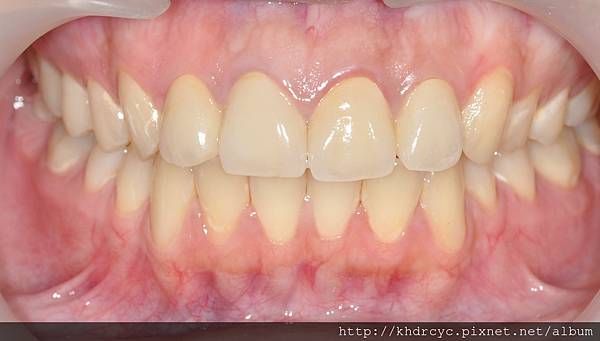

不但牙齒變美變白連口氣都改善了

笑起來也更能自信的露牙齒

唱歌也不用顧忌

仁武的C小姐最訝異的

是美觀能改變這麼多

且在這麼短的時間內就發生